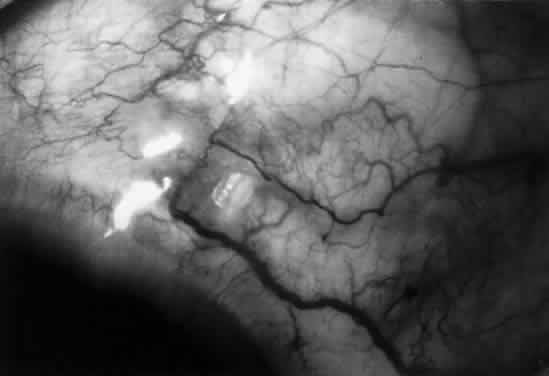

The filtration site is placed posteriorly near the equator in the latest generation of shunts. The morphologic features of these blebs are different from those of functional blebs at the limbus, as seen with a trabeculectomy. They are typically thick-walled, with prominent conjunctival vascularity, and are elevated over the reservoir (Fig. 1). Although the silicone tube and PMMA plates of the Molteno shunt are biologically inert and do not produce tissue necrosis, a thick fibrous capsule envelops the reservoir and tube (Fig. 2)25–29

Fig. 1. Thick vascular bleb over single-plate Molteno shunt.